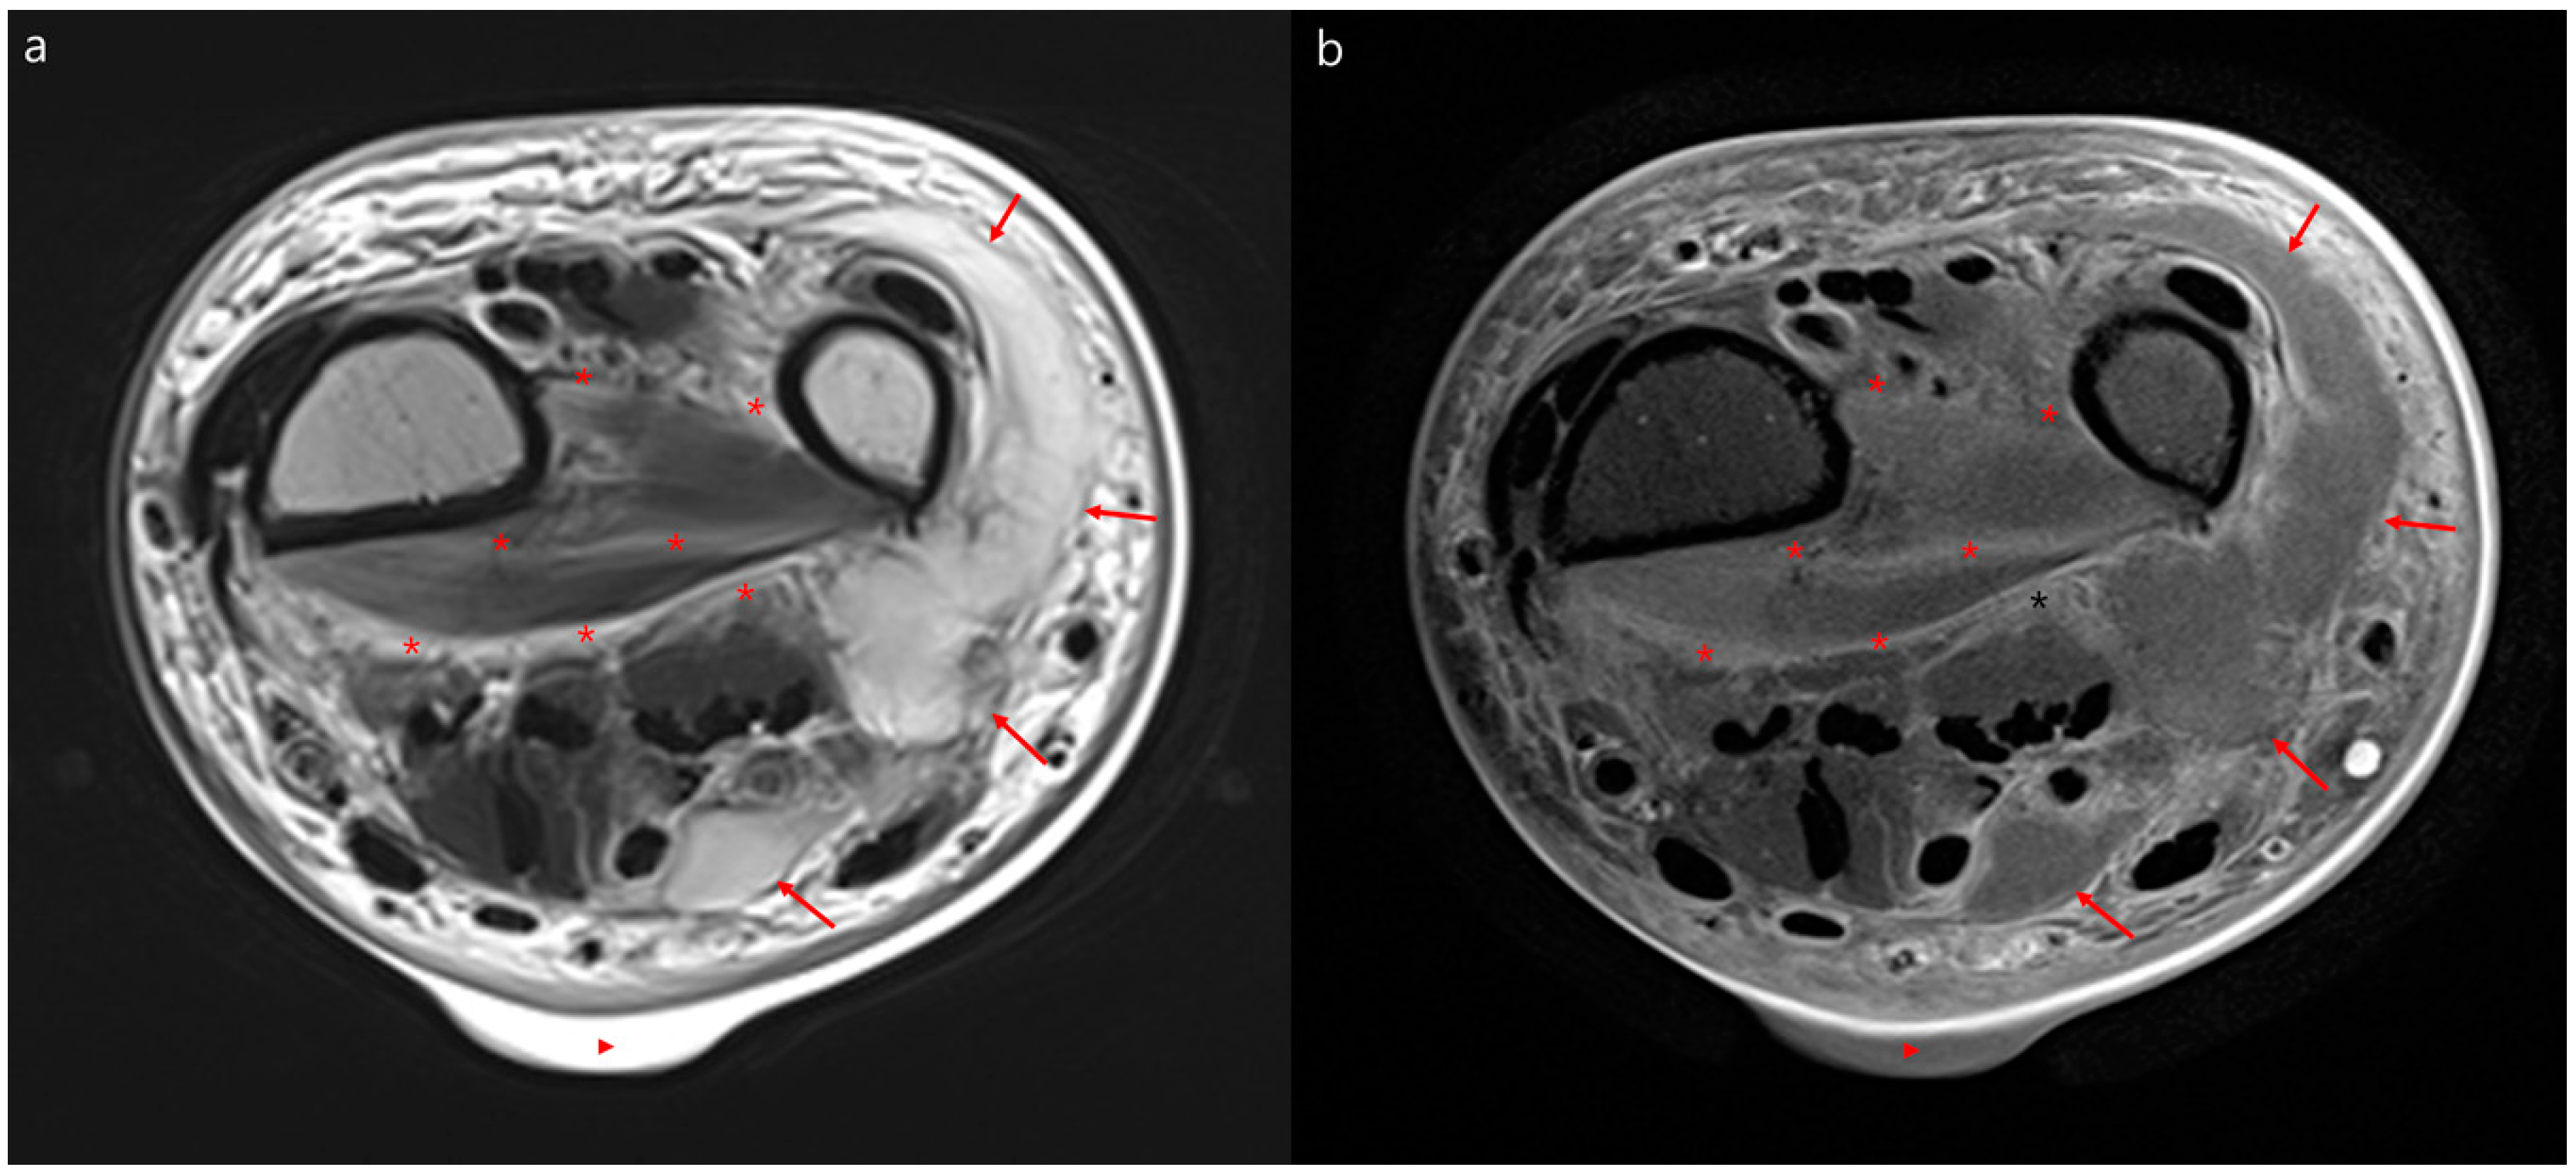

자기 공명 영상(MRI)은 연조직을 보는 데 컴퓨터 단층 촬영(CT)보다 우수하며, 약 93%의 괴사성 근막염 사례를 감지할 수 있다.[15] 특히 괴사성 근막염과 봉와직염을 구별할 수 있는 깊은 근막의 체액을 찾는 데 유용하다.[15] 깊은 근막에 체액이 고이거나 조영제로 두꺼워지거나 조영 증강이 나타나면 괴사성 근막염을 강력하게 의심해야 한다. 그러나 MRI는 CT보다 훨씬 느리고 널리 사용되지 않는다.[15] 신장 문제가 있는 환자에게는 사용에 제한이 있을 수 있다.[15]